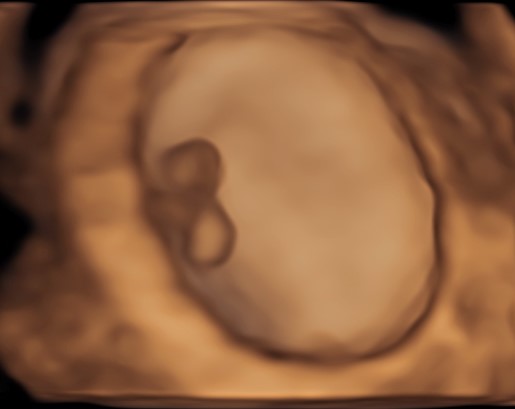

4D/5D/HD Ultrasound Gallery

Gallery